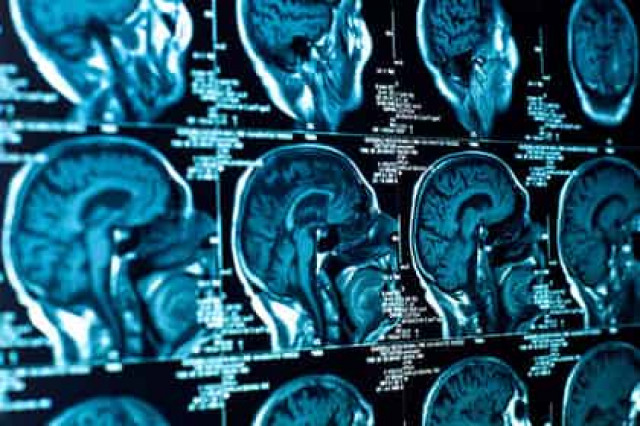

Для эксперимента отобрали 108 молодых здоровых людей. Им предлагались различные ролевые игры, связанные с финансовыми рисками, принятием экономических решений, стрессом от потери состояния. При ответе на вопросы мозг добровольцев исследовался с помощью специальной аппаратуры.

Выяснилось, что более спокойно относящиеся к риску и его последствиям имеют лучшие функциональные связи между миндалиной и префронтальной корой. Также более склонные к риску имели большее количество серого вещества.